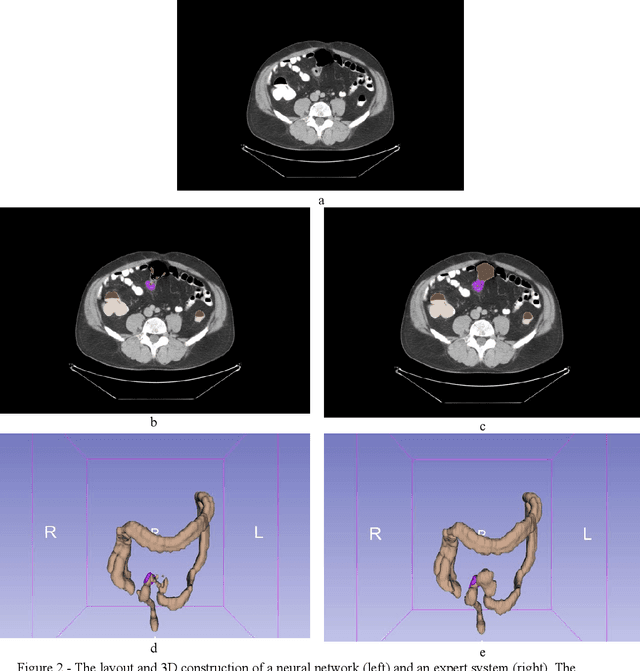

Colorectal cancer is the third-most common cancer in the Western Hemisphere. The segmentation of colorectal and colorectal cancer by computed tomography is an urgent problem in medicine. Indeed, a system capable of solving this problem will enable the detection of colorectal cancer at early stages of the disease, facilitate the search for pathology by the radiologist, and significantly accelerate the process of diagnosing the disease. However, scientific publications on medical image processing mostly use closed, non-public data. This paper presents an extension of the Medical Decathlon dataset with colorectal markups in order to improve the quality of segmentation algorithms. An experienced radiologist validated the data, categorized it into subsets by quality, and published it in the public domain. Based on the obtained results, we trained neural network models of the UNet architecture with 5-part cross-validation and achieved a Dice metric quality of $0.6988 \pm 0.3$. The published markups will improve the quality of colorectal cancer detection and simplify the radiologist's job for study description.